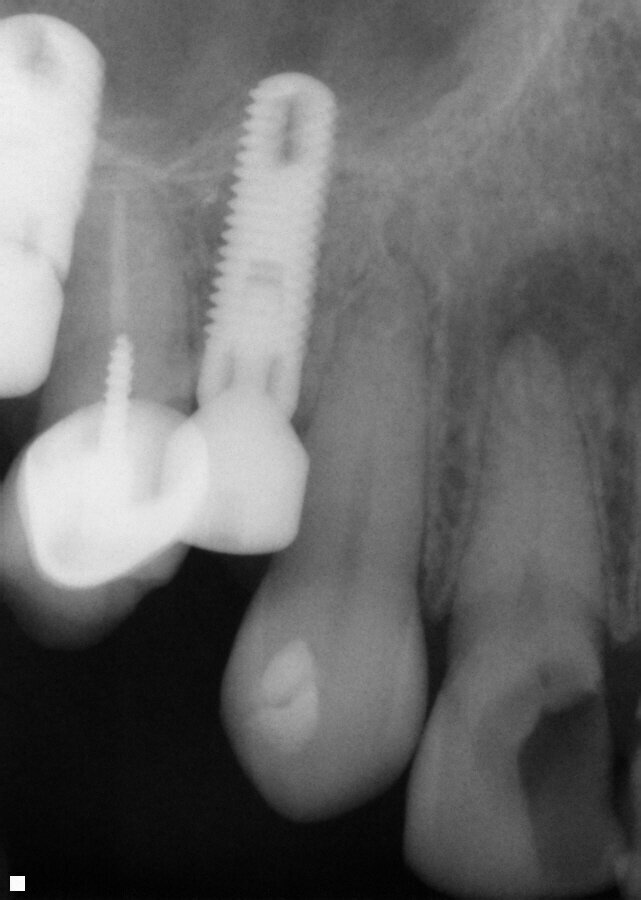

Fig. 16: Patient presented with percussion and hot sensitivity on the lower first molar that she reported was increasing over the past week.

A 62-year-old female patient presented with the complaint of sensitivity to chewing and hot foods and beverages on tooth 19 (mandibular left first molar) that had been increasing over the past week. Examination noted an old amalgam on the tooth that appeared intact to the explorer. A radiograph was taken, and slight apical widening was noted on both root apex on the tooth (Fig. 16). The tooth was responsive to testing with heat with a prolonged response of a minute or so. No cold sensitivity was elicited when tested. Both teeth also tested to slight responsiveness to percussion stimuli. Patient was informed that based on the tooth’s presentation it was recommended that endodontic treatment was indicated. The patient agreed to treatment.

The tooth was isolated with rubber dam, and the old amalgam restoration was removed and access performed with canal orifice identification. The SX file (ExactTaperH DC) was utilized to enlarge the canal orifice and aid in further file instrumentation. The three canals were explored with stainless steel hand files to working length starting at a size 10 and progressing to a size 20. The canals were then instrumented to working length with the GP file. Each canal was instrumented with ExactTaperH DC files starting with the S1, then followed by the F1, F2 and F3 in the mesial-buccal and distal-buccal canals of the molar. The canals were irrigated by alternating between sodium hypochlorite 3 percent (Vista Apex) and 17 percent EDTA solution (Vista Apex) during instrumentation and at completion. The canals were then dried with paper points (ExactTaperH DC) matching the size of the final file used. Bioceramic Root Canal sealer was mixed and dispensed on a pad. A gutta-percha cone (ExactTaperH DC) matching the final file size for each canal was coated with sealer and each canal was obturated in a single cone technique. The excess cones were cut off at the canal orifice and obturation was completed (Fig. 16). A temporary restoration (Fermit-N, Ivoclar Vivadent, Buffalo, N.Y.) was placed into the tooth and the patient was appointed to restore the tooth.